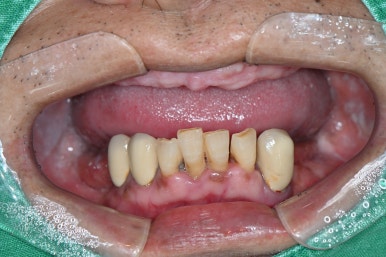

강남 풀아치 임플란트 (좌: 2024년 7월 1일, 우:2024년 9월 23일 완성)

좌: 틀니를 착용하고 엑스레이를 찍은 모습, 우: 풀아치 임플란트를 식립한 직후 (2024년 7월 1일)

디지털 풀아치 임플란트가 완성된 모습

최종 완성된 디지털 풀아치 임플란트 (상악)